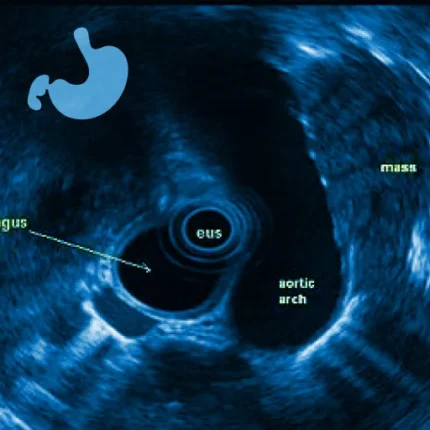

Endosonografia Lublin – nowoczesna metoda diagnostyczna

Endosonografia Lublin Usługi świadczone w ramach kontraktu NFZ (hospitalizacja jednodniowa) oraz komercyjnie. EUS (z j. ang. endoskopowa ultrasonografia), czyli prościej endosonografia – jest to metoda badania przewodu pokarmowego i struktur z nim sąsiadujących, łącząca w sobie dwie metody badania – „klasyczną” endoskopię i ultrasonografię. Innymi słowy, za pomocą jednego aparatu (endosonografu) wykonuje się zarówno badanie […]